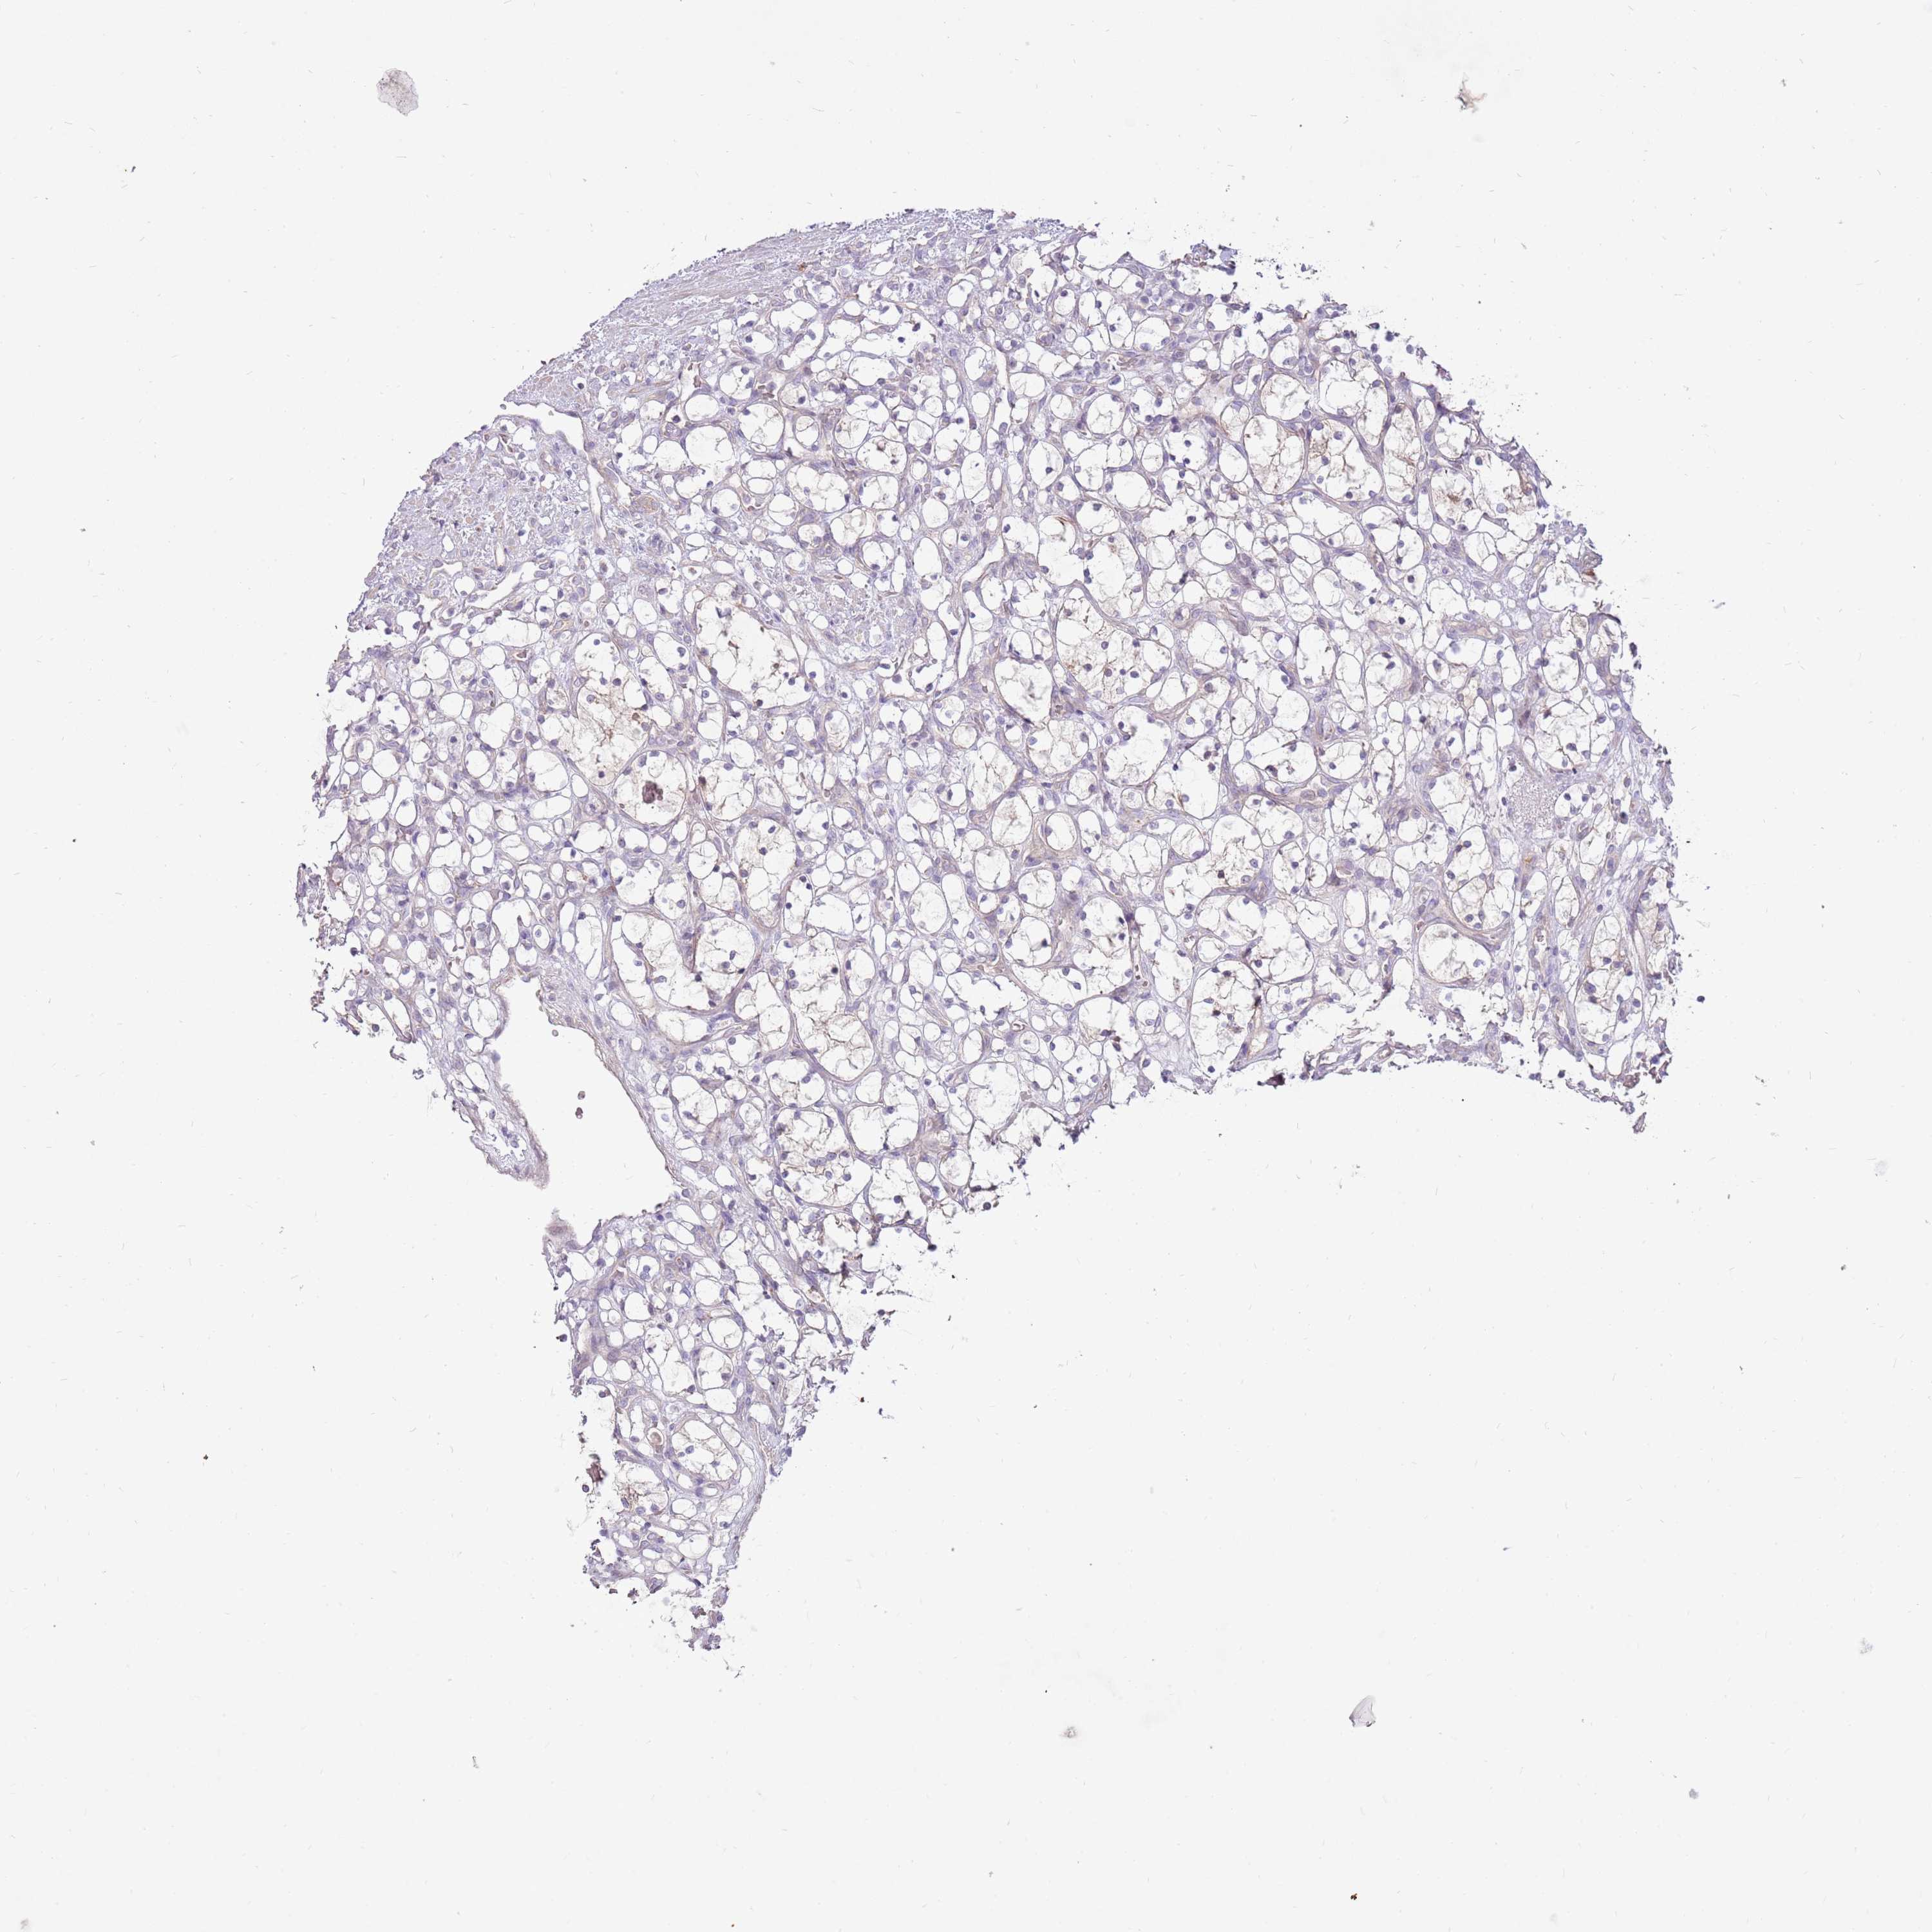

KIDNEY RENAL CLEAR CELL CARCINOMA (VALIDATION) - Interactive survival scatter ploti

The Survival Scatter plot shows the clinical status (i.e. dead or alive) for all individuals in the patient cohort, based on the same data that underlies the corresponding Kaplan-Meier plots. Patients that are alive at last time for follow-up are shown in blue and patients who have died during the study are shown in red.

The x-axis shows the expression levels (FPKM) of the investigated gene in the tumor tissue at the time of diagnosis. The y-axis shows the follow-up time after diagnosis (years). Both axes are complimented with kernel density curves demonstrating the data density over the axes. The top density plot shows the expression levels (FPKM) distribution among dead (red) and alive patients (blue). The right density plot shows the data density of the survived years of dead patients with high and low expression levels respectively, stratified using the cutoff indicated by the vertical dashed line through the Survival Scatter plot. This cutoff is automatically defined based on the FPKM cutoff that minimizes the p-score. The cutoff can be changed by dragging the vertical line or by entering a cutoff value in the square labeled "Current cut-off".

Under the Survival Scatter plot the p-score landscape (black curve; left axis) is shown together with dead median separation (red curve; right axis). Dead median separation is the difference in median mRNA expression between patients who have died with high and low expression, respectively. It is calculated as follows: median FPKM expression of dead patients with high expression - median FPKM expression of dead patients with low expression. This is intended to aid the user in visually exploring custom cutoffs and the associated p-scores and dead median separation.

Individual patient data is displayed and can be filtered by clicking on one or more of the category buttons on the top of the page. Categories describing expression level and patient information include: high, low, alive, dead, female, male and tumor stages. The scale of the x-axis can be toggled between linear and log-scale by clicking on the "x log" button. Mouse-over function shows TCGA ID, patient information and mRNA expression (FPKM) for each patient.

& Survival analysisi

Kaplan-Meier plots summarize results from analysis of correlation between mRNA expression level and patient survival. Patients were divided based on level of expression into one of the two groups "low" (under cut off) or "high" (over cut off). X-axis shows time for survival (years) and y-axis shows the probability of survival, where 1.0 corresponds to 100 percent.

LRFN3 is not prognostic in Kidney Renal Clear Cell Carcinoma (validation)

Best expression cut offi

Based on the FPKM value of each gene, patients were classified into two groups and association between prognosis (survival) and gene expression (FPKM) was examined. The best expression cut-off refers the FPKM value that yields maximal difference with regard to survival between the two groups at the lowest log-rank P-value. Best expression cut-off was selected based on survival analysis .

When clicking on this number, the vertical dashed line indicating cut-off, the interactive survival plot, and the Kaplan-Meier curve will be adjusted to show results based on the best expression cut-off.

: 2.88

Median expressioni

Median expression refers to the median FPKM value calculated based on the gene expression (FPKM) data from all patients in this dataset. When clicking on this number, the vertical dashed line indicating cut-off, the interactive survival plot, and the Kaplan-Meier curve will be adjusted to show results based on the median expression.

: N/A

P scorei

Log-rank P value for Kaplan-Meier plot showing results from analysis of correlation between mRNA expression level and patient survival.

N/A

TCGA RNA samplesi

RNA-seq data is reported as average FPKM (number Fragments Per Kilobase of exon per Million reads), generated by the The Cancer Genome Atlas (TCGA) .

Normal distribution across the dataset is visualized with box plots, shown as median and 25th and 75th percentiles. Points are displayed as outliers if they are above or below 1.5 times the interquartile range. FPKM values of the individual samples are presented next to the box plot.

Average pTPM 3.6

Number of samples 100